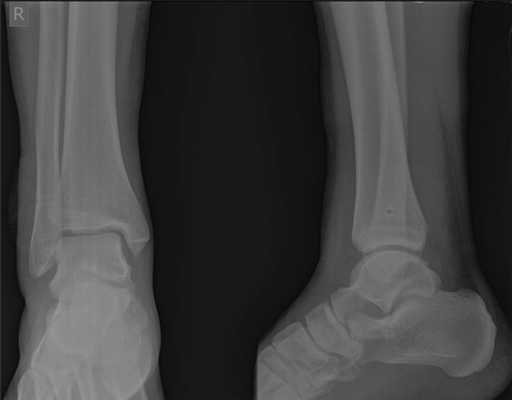

При детальном изучении снимков определяется увеличение межберцовой щели до 7,5 мм, уменьшения зоны перекрытия большеберцовой и малоберцовой костей до 5 мм, отсутствие на стороне поражения перекрытия тени таранной кости и малоберцовой кости.

На рентгенограмме костей правого и левого голеностопных суставов в прямой проекциии, снимки стоя - справа определяются признаки повреждения дистального межберцового синдесмоза - степень взаимного перекрытия берцовых костей 5мм (в норме больше 6мм) увеличенное большеберцовое - малоберцовое пространство - 7.5мм (в норме до 6мм).